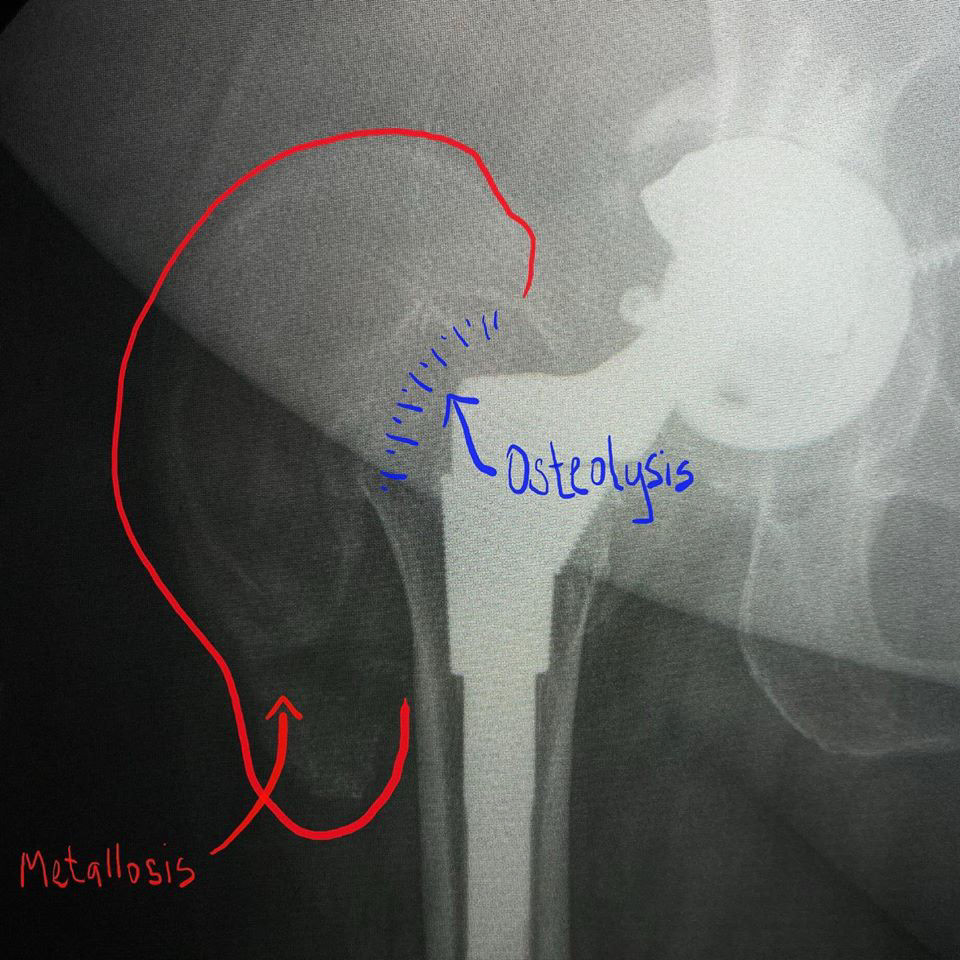

Metallosis! Hardware failure, especially in hip arthroplasties, can be a result of the following pathologies: 1. Simple aseptic loosening – diagnosed with progressive more than 2mm peri-hardware or peri-cement lucency and not associated to infection. Lucency about hardware is usually symmetric. 2. Infection – peri-hardware lucency greater than 2mm, but unlike loosening, usually asymmetric, focal and destructive. 3. Particle disease – previously discussed and related to debris released by hardware which in turn incites osteolysis of the surrounding bone. 4. Metallosis – also known as hardware pseudotumor and usually co-existing with particle disease and osteolysis. In imaging, metallosis is seen as a soft tissue pseudo mass created by metal debris. This mass usually is dense on radiographs and CT, due to the presence of metal. This case shows both particle disease with osteolysis at the greater trochanter and metallosis at the soft tissue adjacent to the greater trochanter. #mskrad #mskradiology #radiology #radiologia #radres #radtech #radiologyeducation #hipprosthesis #radiologyresident #msk🧞♂️